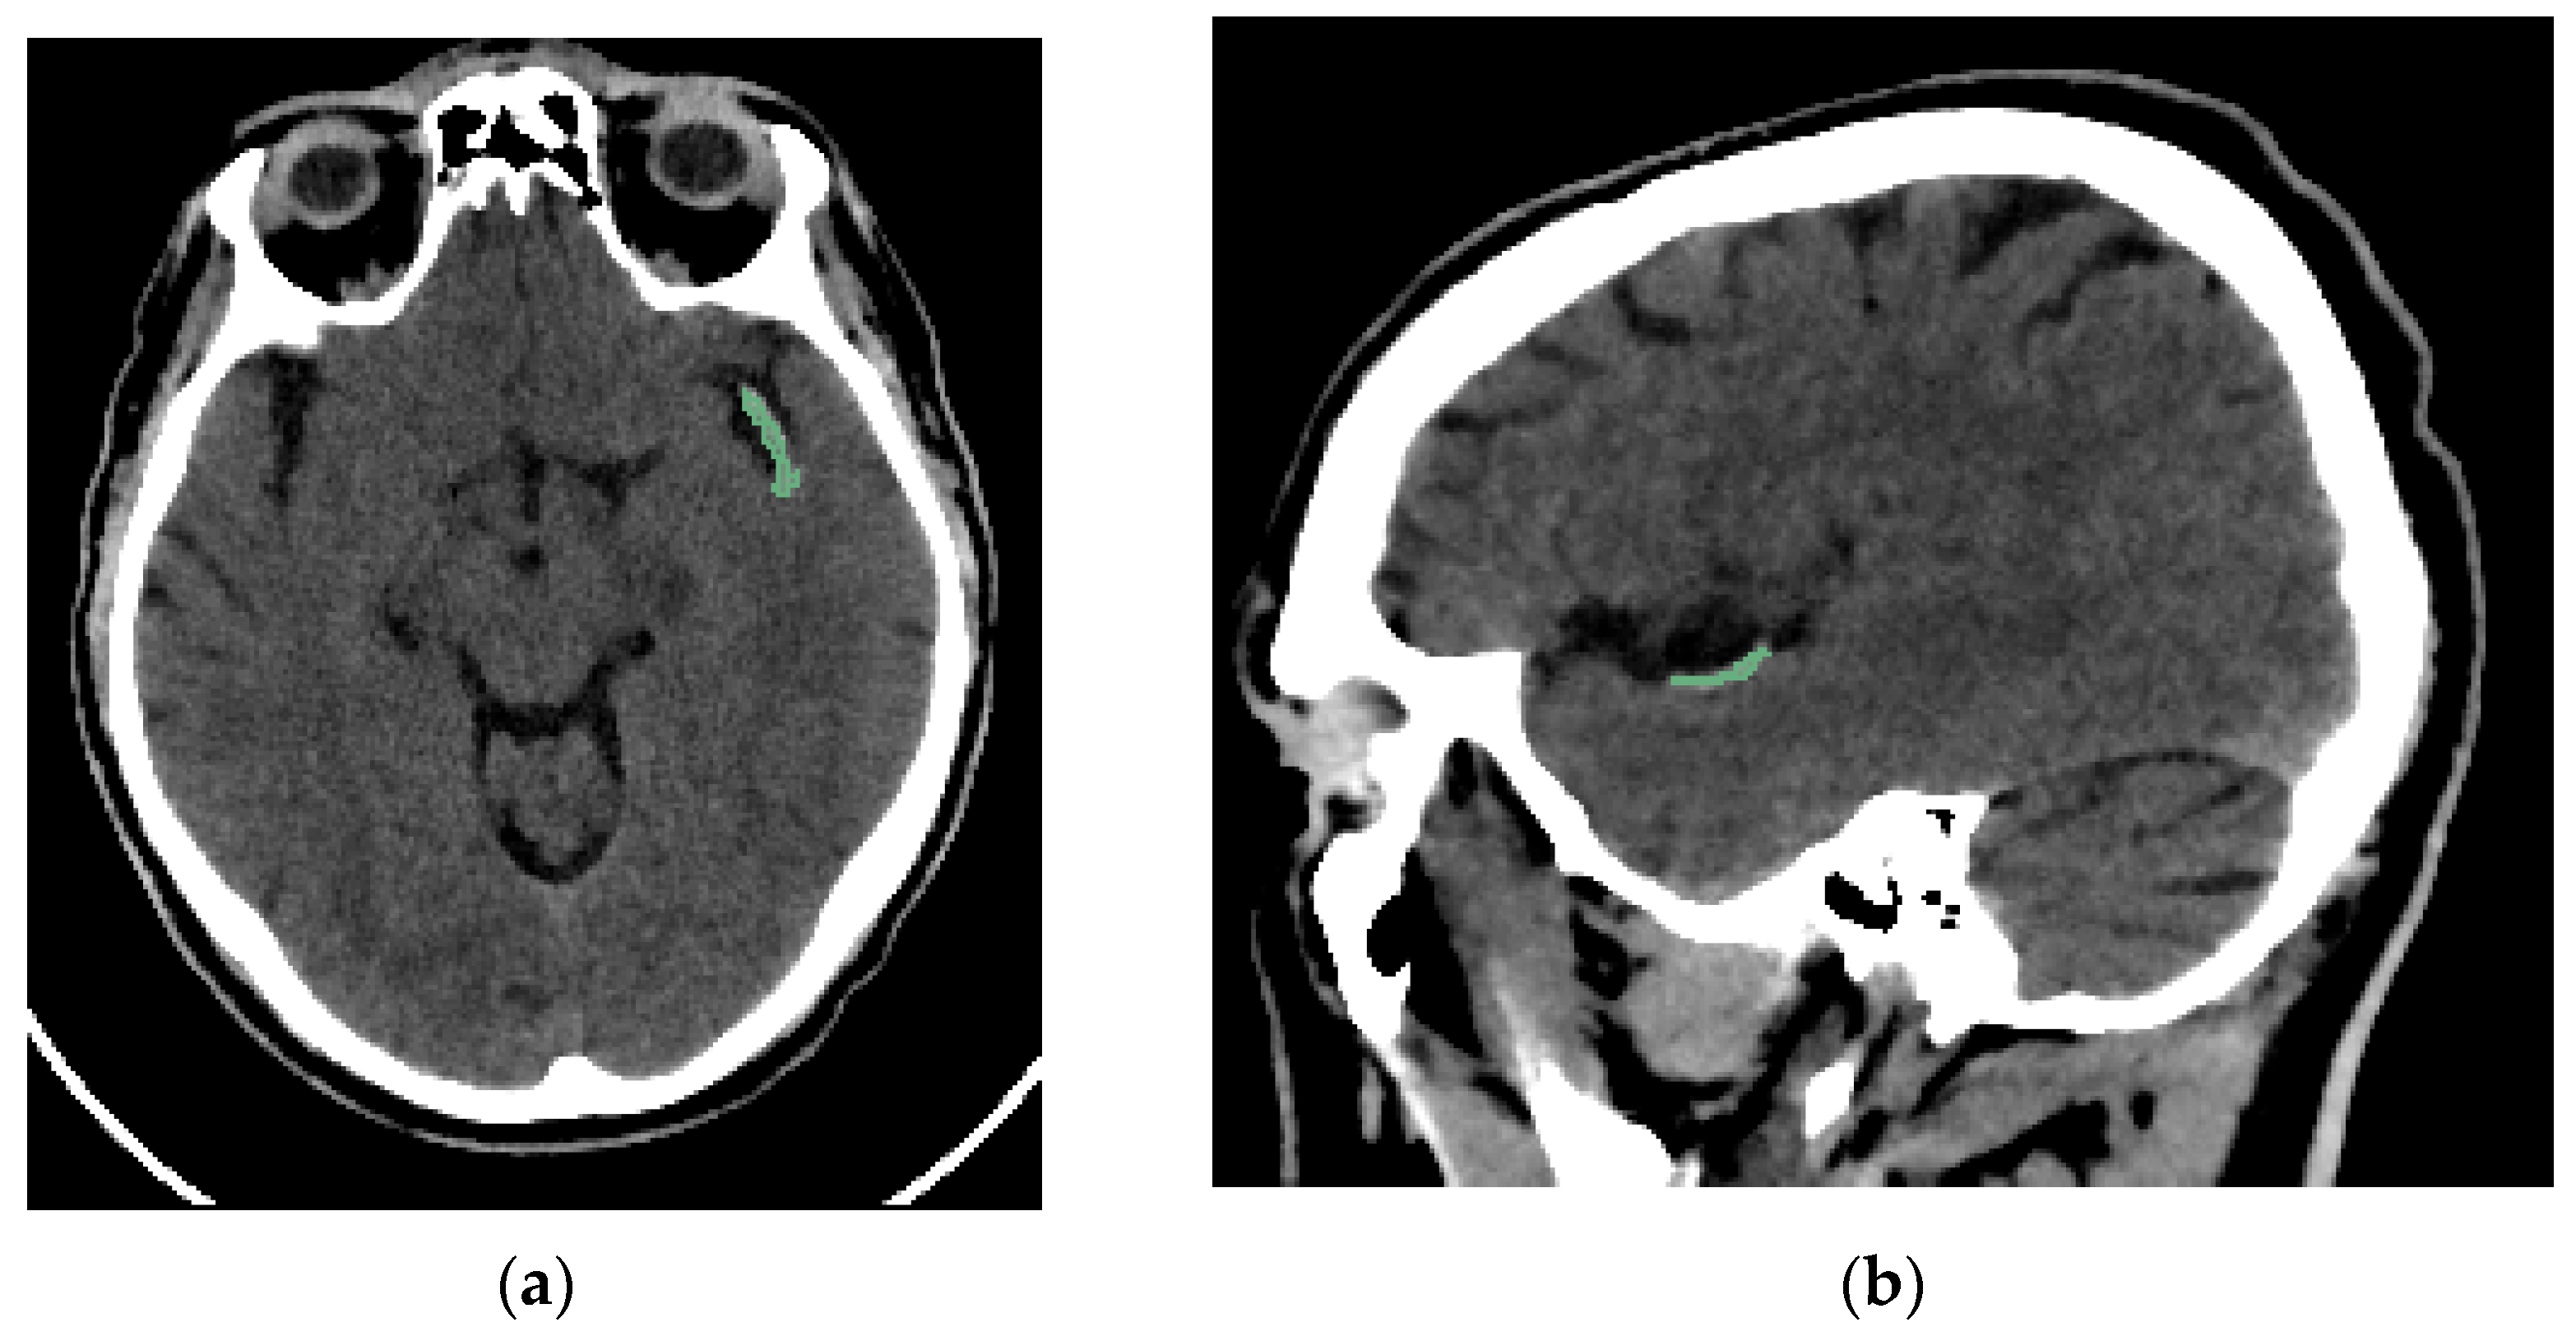

Two interventional neuroradiologists and a radiology resident who had undergone specialized training performed semi-automated segmentation of each thrombus. The segmentation was conducted using the open-access software 3D Slicer (version 5.2.2, Massachusetts, USA) [16]. The software includes a segmentation tool (Level Tracing tool) that enables semi-automatic segmentation based on automatic edge detection. The region of interest segmented was the clot visible on NCCT in patients with AIS (Figure 2). Segmentation was performed in the axial, sagittal, and coronal planes (Figure 3). The window width and center were set to 100 and 50 HU, respectively.

Figure 2.

Brain NCCT of the same patient as in Figure 1, with the thrombus segmented. The segmentation was performed using the “Level Tracing” tool of 3D Slicer. (a) Axial NCCT with thrombus segmented. (b) Sagittal NCCT of the same patient with the thrombus segmented.